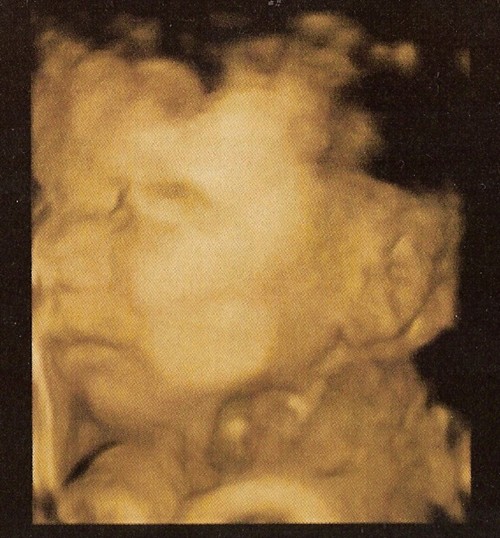

Vissza: Gyermekek / magzatok kor szerint